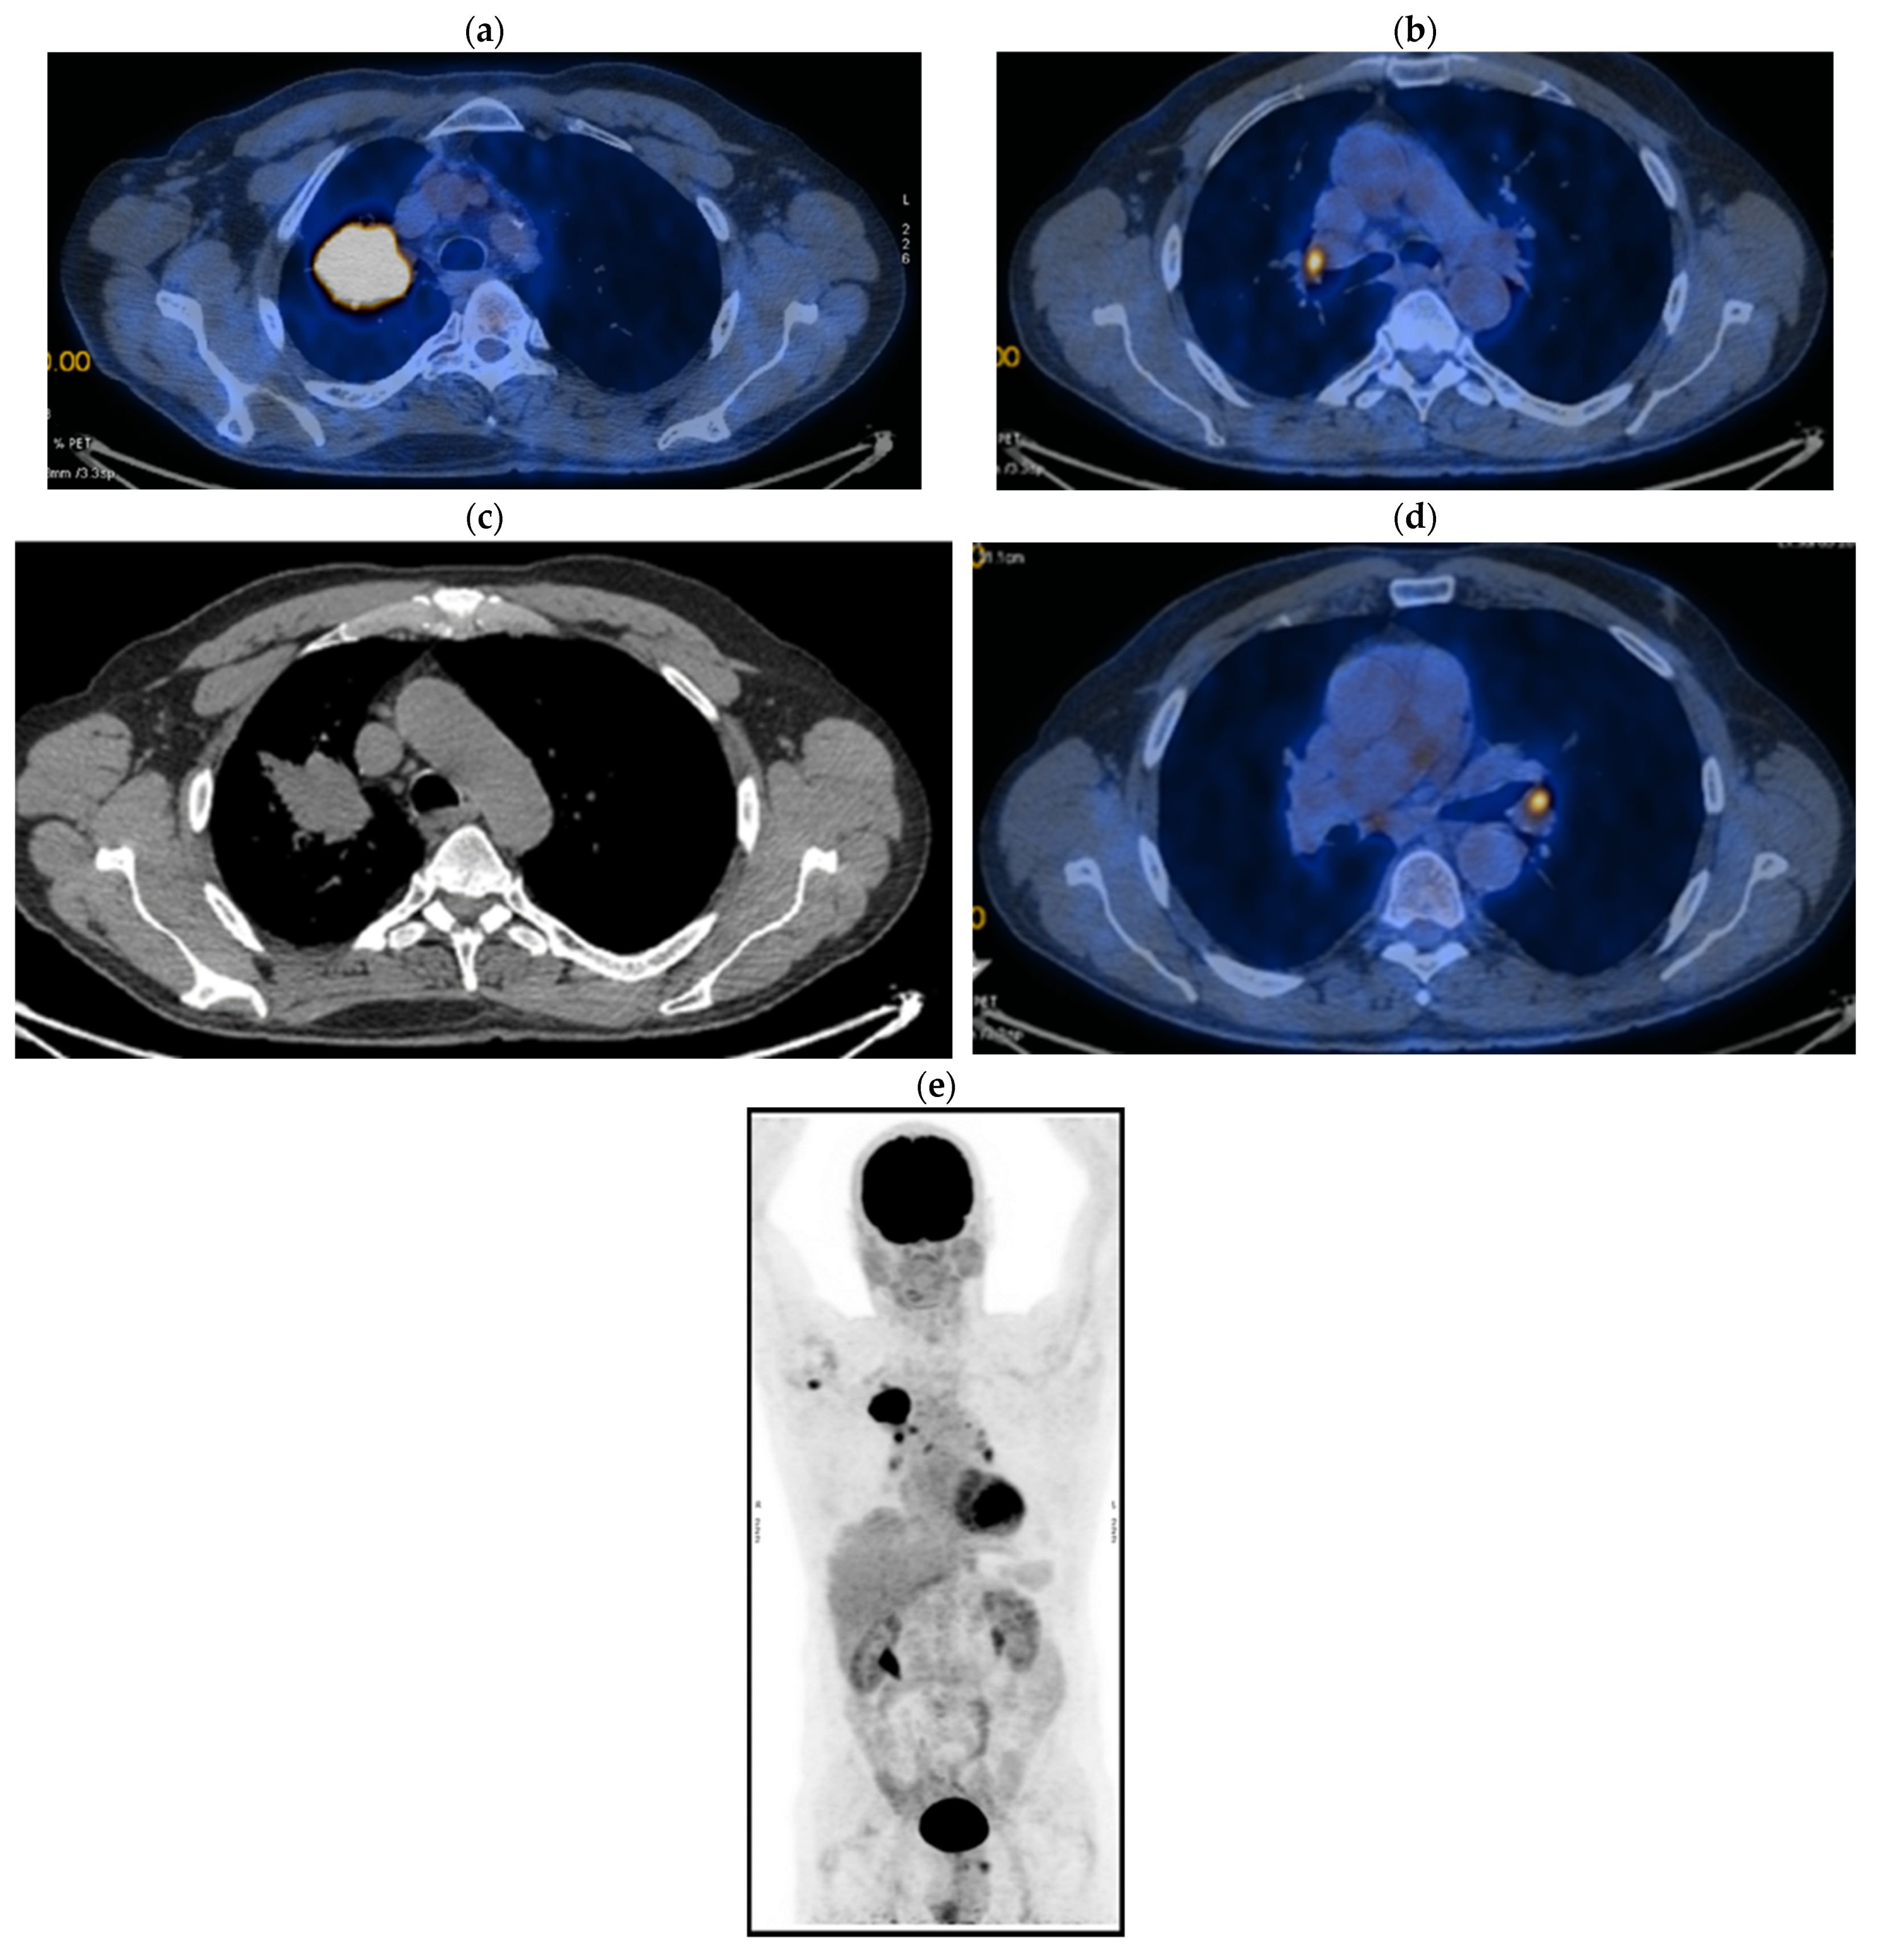

2. Case Presentation

2.1. Systemic Third-Line Therapy (4xDocetaxel) Was Initiated 04–07/2020

2.2. Monitoring 2022: Oncological Commission 1910/16.08.2022

2.3. Oncological Committee 07/25/2023 Recommended

- Consider rescue re-irradiation (SBRT), taking into account the current primary tumor dimensions of 24 × 34.2 mm on PET CT from 06/2023 and also the total dose previously administered (08–09/2020), the previously applied fractionation, the time between the two irradiations, the cellular repair time and the dose constraints for the organs at risk.